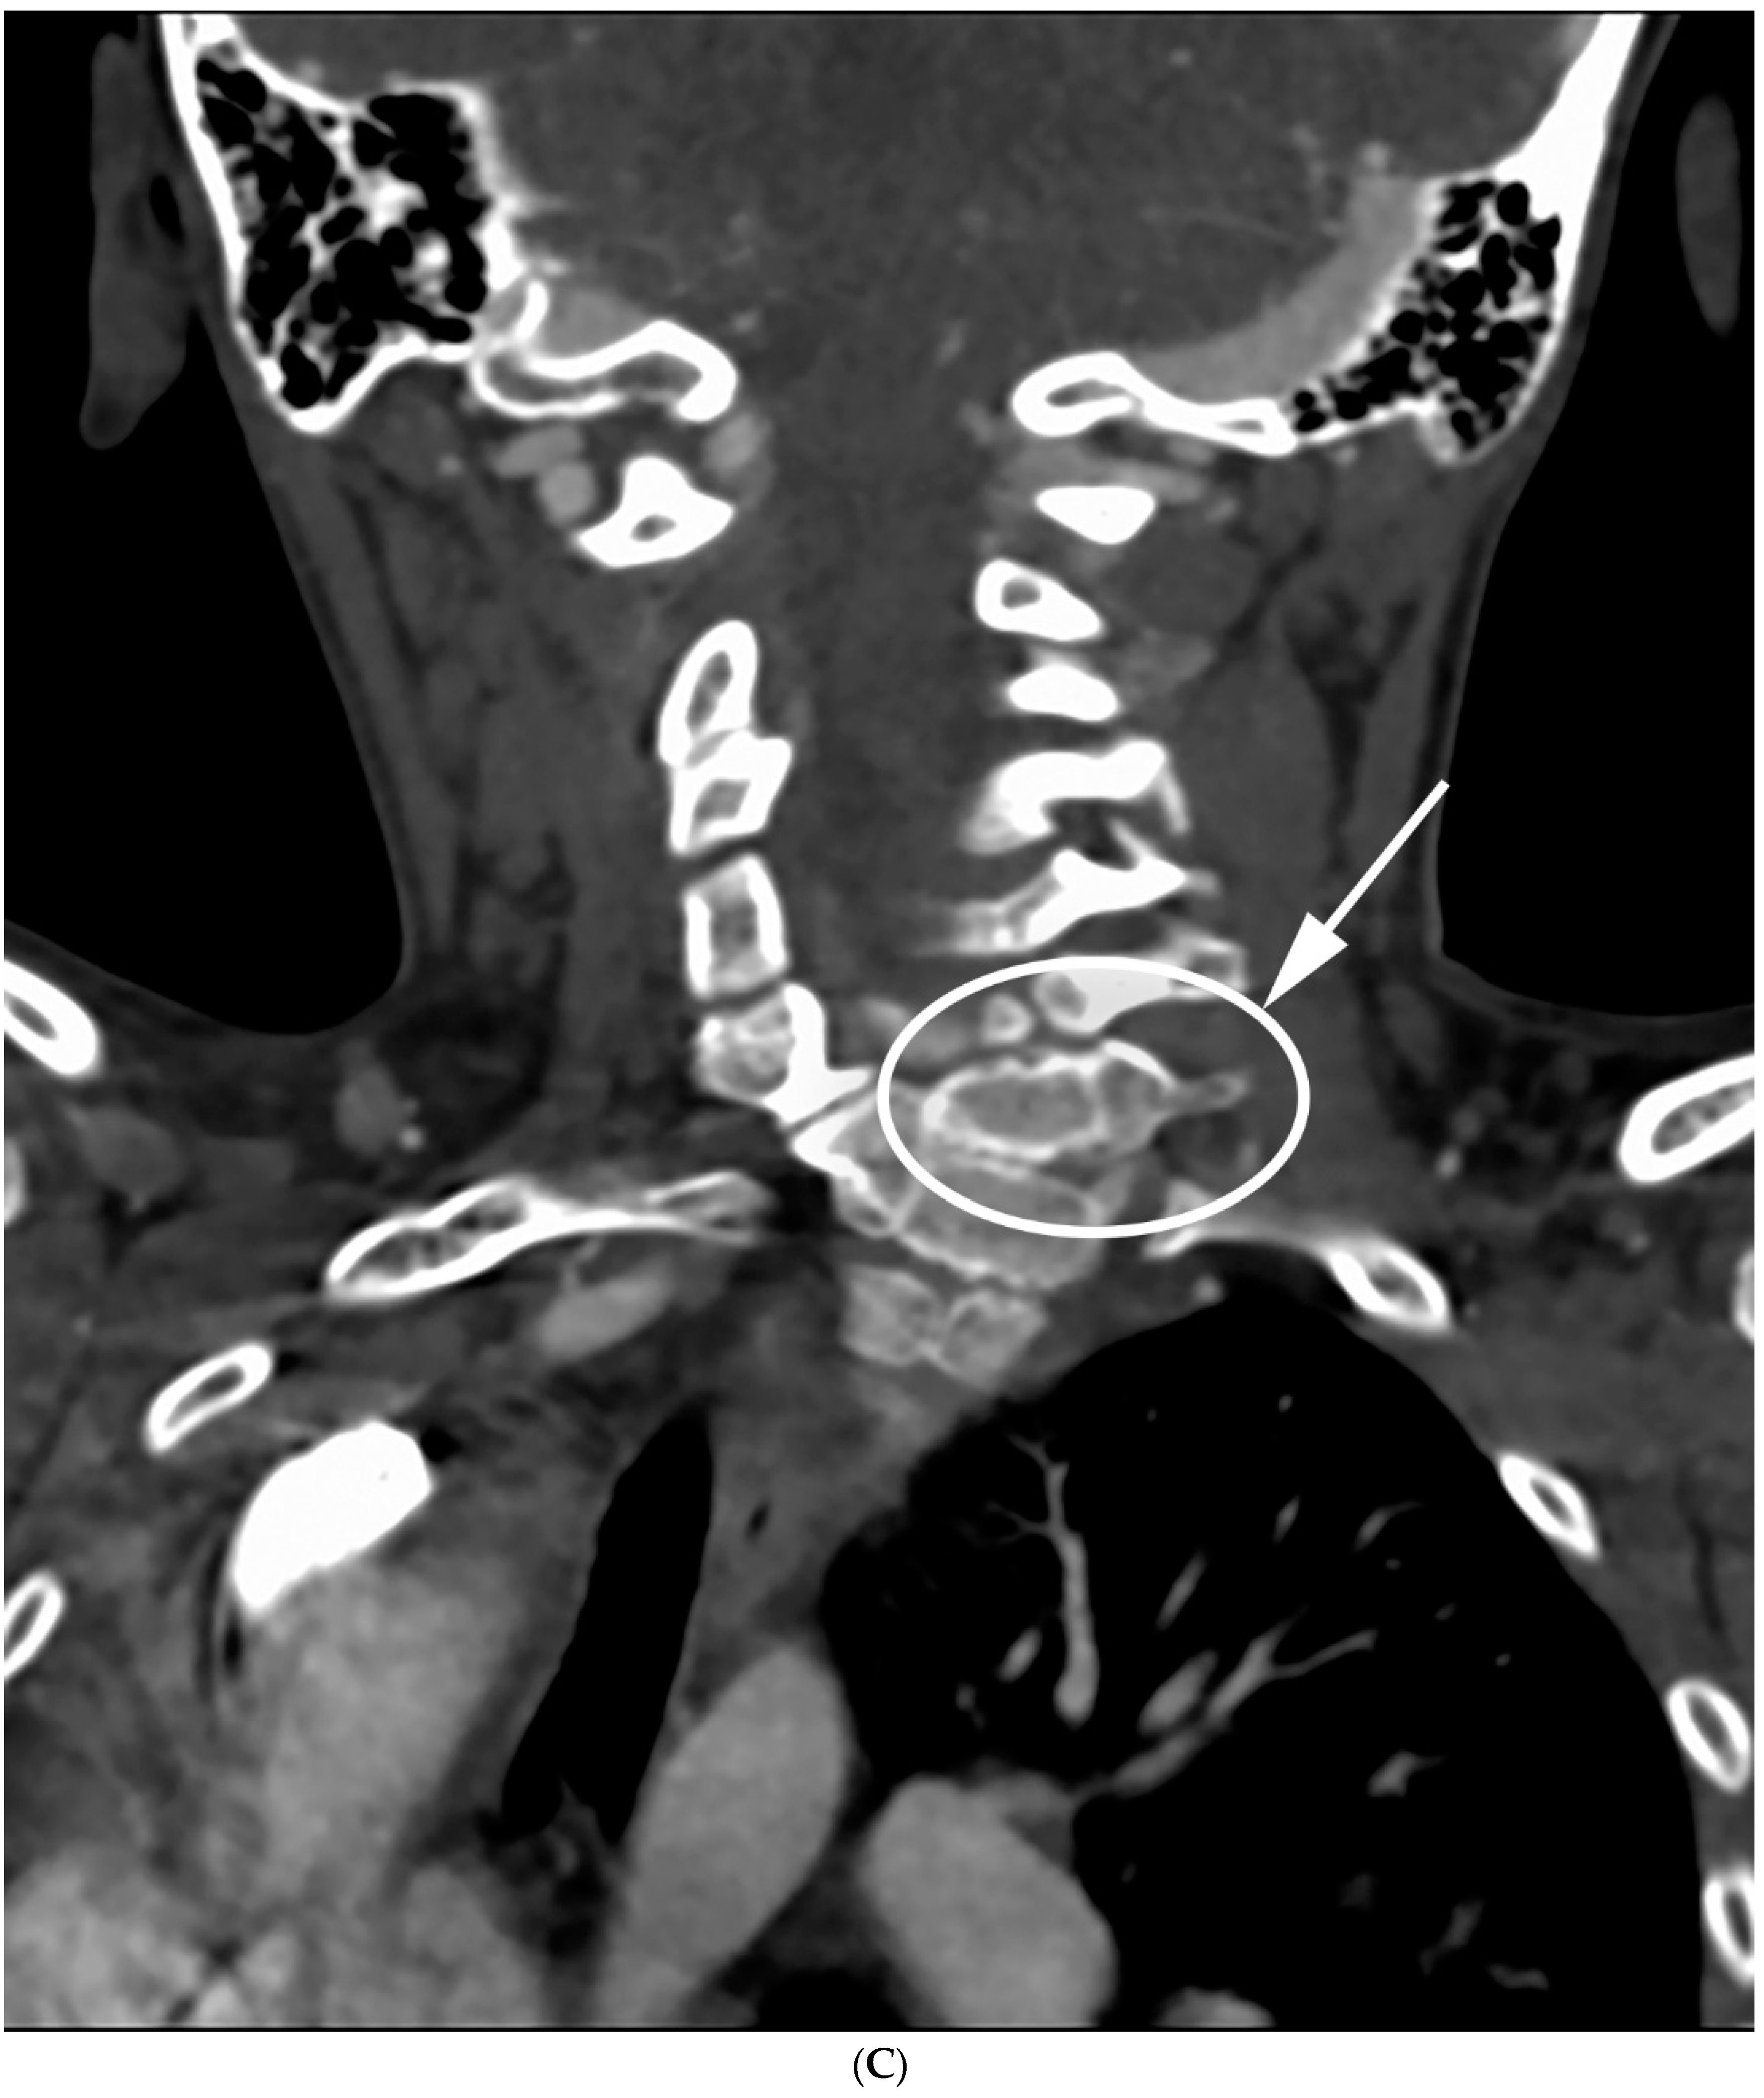

Figure 5.

(A,B) Initial PA and lateral radiograph of a 7-year-old child with a 19° cervicothoracic scoliosis and T1 slope of 31°. (C,D) Follow-up PA and lateral radiographs showing progression of the curve to 38° over 8 years.

Figure 6.

(A,B) Initial PA and lateral radiograph of a 2-year-old child presenting with 17° of scoliosis at the cervicothoracic junction and T1 slope of 11°. (C,D) Follow-up radiographs showing a stable curve approximating 18° 4 years later.